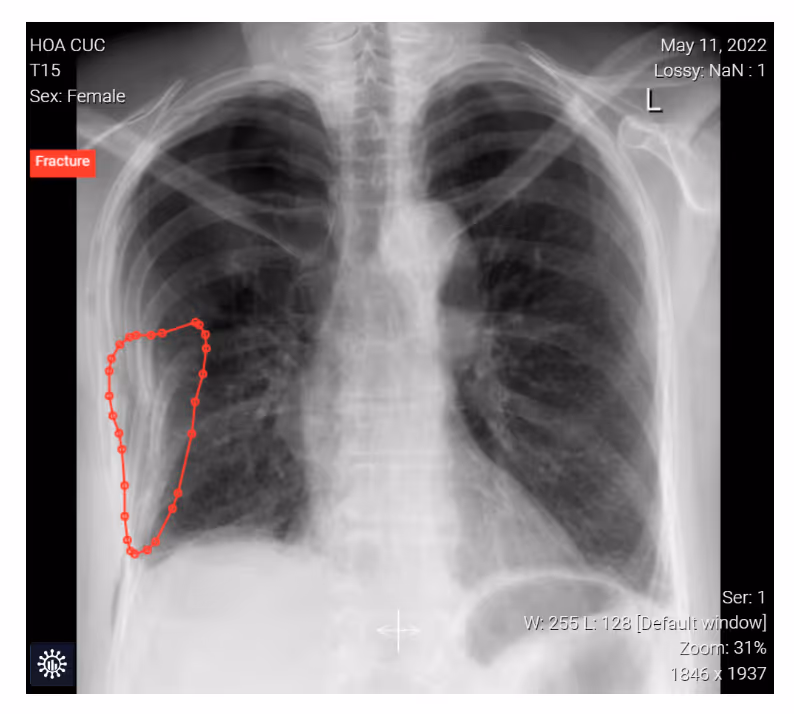

- A 55-year-old female toppled to the right side experiencing thoracic tenderness and mild shortness of breath.

- Image findings:

- Partially displaced rib fractures and a pneumothorax on the right side.

- Fractures of the right ribs 3-8 were obvious with a displacement of the 5th and 6th ribs.

- The thin pleural line and the lack of the pulmonary vessels in the right apex visibly reflect a pneumothorax.

- Subcutaneous emphysema of the thoracic wall.